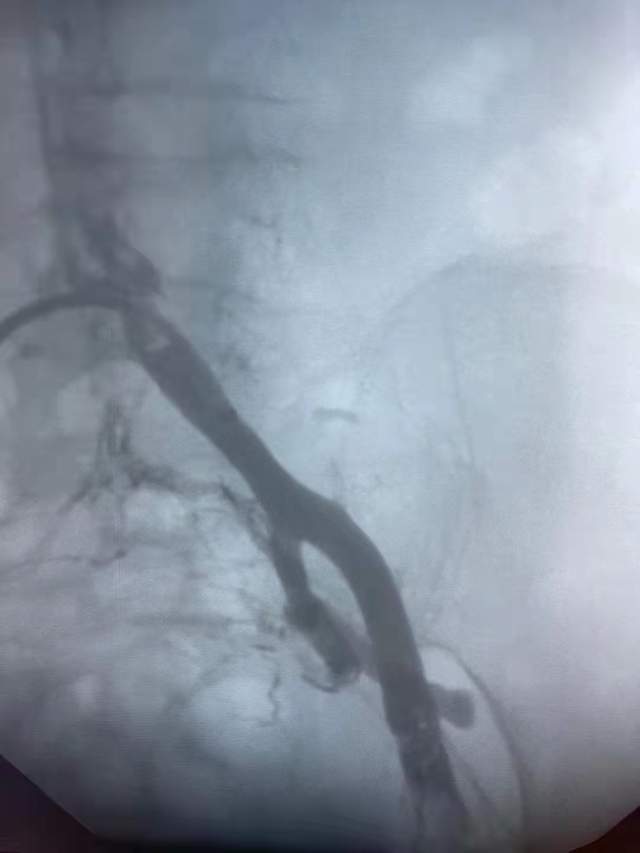

术前许玉华主任团队制定了详细的诊疗计划和周密的手术方案,术中造影示:左侧髂总静脉、左侧髂内静脉、左侧髂外静脉见多发充盈缺损,造影剂回流下腔静脉不畅,予以碎栓、抽栓术,抽出大量的血栓。术后,患者下肢水肿减轻。